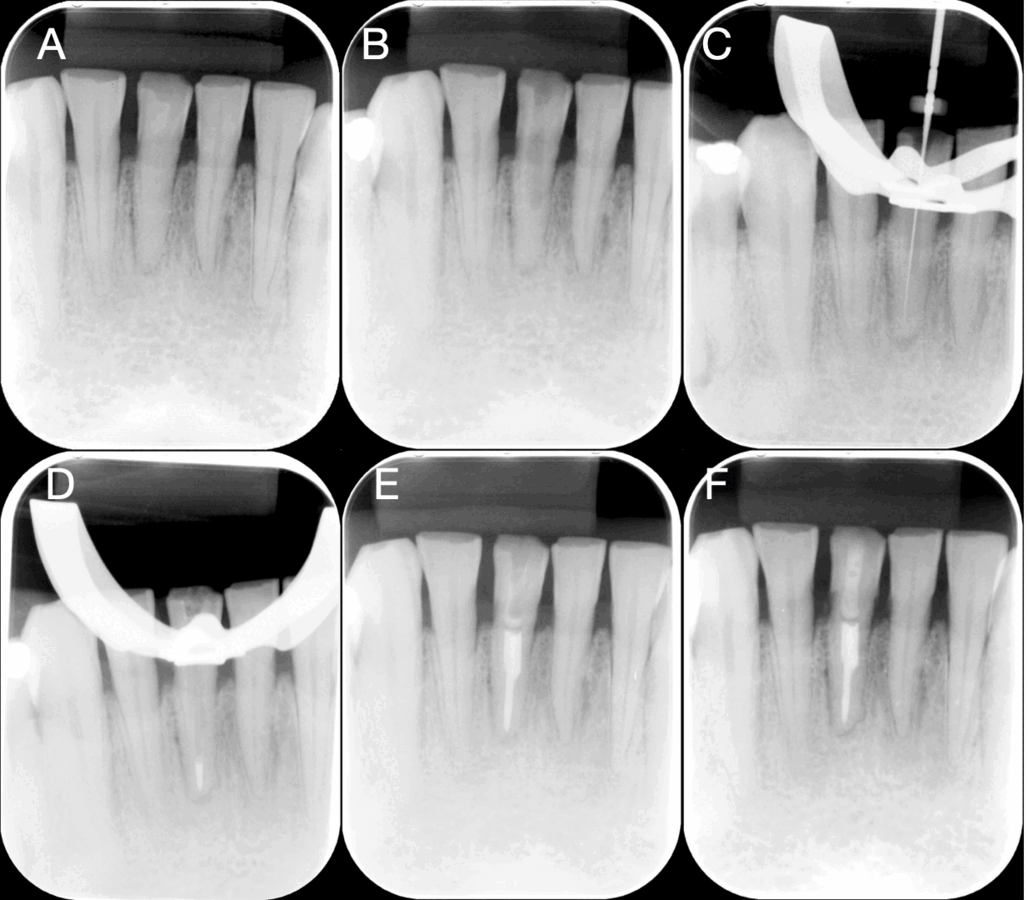

El incisivo central mandibular mostró una respuesta positiva tanto a las pruebas de percusión vertical como a las de percusión horizontal, y ninguna respuesta a la prueba de vitalidad pulpar térmica. La radiografía periapical inicial (figura 1A) demostró la presencia de obliteración severa del conducto radicular a nivel de la pulpa cameral y radicular, en comparación con los incisivos central y lateral adyacentes. El diente 41 presentaba evidencia radiográfica de periodontitis apical. Se realizó una TCHC de maxilares con un FOV 16×18 cm en un tomógrafo (GIANO HR, NewTom®, Imola, Italia). Las imágenes tomográficas confirmaron la presencia de una calcificación severa del conducto y patología periapical (figura 2).

Figura 1. Control radiográfico: A) Radiografía periapical inicial en donde se observa obliteración completa del conducto; B) Radiografía de control de acceso endodóntico con fresa ATEC hasta tercio medio; C) Radiografía de control de conductometría con lima K10; D) Radiografía de control de conometría técnica de onda continua de calor; E) Radiografía de control de obturación del conducto radicular; F) Radiografía periapical de control de un año después del tratamiento.

Se obtuvo el consentimiento informado del paciente y se procedió a realizar la prueba de la guía para verificar el ajuste correcto sobre las superficies incisales de los dientes anteriores mandibulares. Se administró anestesia local infiltrativa con vasoconstrictor y se realizó una marca a través de la guía para identificar el punto de acceso con una mina de lápiz. Se eliminó el esmalte de forma mínimamente invasiva hasta exponer la dentina, utilizando una fresa de diamante redonda (1014, Microdont®, Sao Paulo, Brasil). A continuación, la fresa ATEC (figura 3C) se ajustó en un motor endodóntico con una velocidad de rotación de 1000 rpm y 2,5 Ncm de torque; y se accedió hasta el tercio medio radicular, con abundante irrigación y con movimientos hacia dentro y hacia fuera, hasta alcanzar el punto de referencia marcado en la fresa ATEC. Se realizó una radiografía de control del acceso (figura 1B).

La preparación del acceso duró aproximadamente 10 minutos. A continuación, se aisló completamente el diente para el tratamiento endodóntico convencional (figura 3B). Con la magnificación de 1,6x del microscopio quirúrgico (RM-2000 Plus, Rogin Dental®, Shenzhen, China), se localizó el conducto con un explorador endodóntico DG16 y unas limas de preserie de 25 mm (K08 y K10, Maillefer®, Ballaigues, Suiza). Se tomó una radiografía periapical de conductometría para verificar el acceso al conducto radicular (figura 1C). Posteriormente, se irrigó con hipoclorito sódico al 5,25 % y se instrumentó con un sistema reciprocante hasta una R40 (Reciproc, VDW®, Múnich, Alemania). Se realizó una activación sónica final con la punta (Eddy, VDW, Múnich, Alemania) con 5 intervalos de un minuto de hipoclorito de sodio al 5,25 %, irrigación con 5 mL de solución salina y un intervalo de un minuto de solución de ácido etilendiaminotetraacético (EDTA 18 %, Ultradent®, South Jordan, EE. UU.).

A continuación, se realizó una irrigación final con 5 mL de solución salina. El procedimiento se completó con el uso de conos estériles (Reciproc, VDW®, Múnich, Alemania) para el secado. La obturación se realizó con un cono maestro 40/04 (puntas de gutapercha; Coltene®, Langenau, Alemania) utilizando cemento de sellado de conductos a base de resina epoxi amino (AH Plus, Dentsply®, Erlangen, Alemania). Se realizó una radiografía de control de obturación a nivel del tercio apical (figura 1D) y, con la técnica de onda continua de calor (Beefill 2 en 1; VDW®, Múnich, Alemania), se completó la obturación hasta el tercio cameral del conducto radicular. La cavidad de acceso se limpió con un algodón humedecido en etanol y se selló la endodoncia con resina fluida (figura 3D).

Se realizaron controles radiográficos durante todas las fases del tratamiento, llevados a cabo en una única sesión, observándose una adecuada obturación tridimensional hasta la longitud de trabajo (figura 1E). El control a distancia se efectuó un año después del tratamiento endodóntico, tomando como resultado la ausencia de sintomatología y la neoformación ósea a nivel periapical (figura 1F).